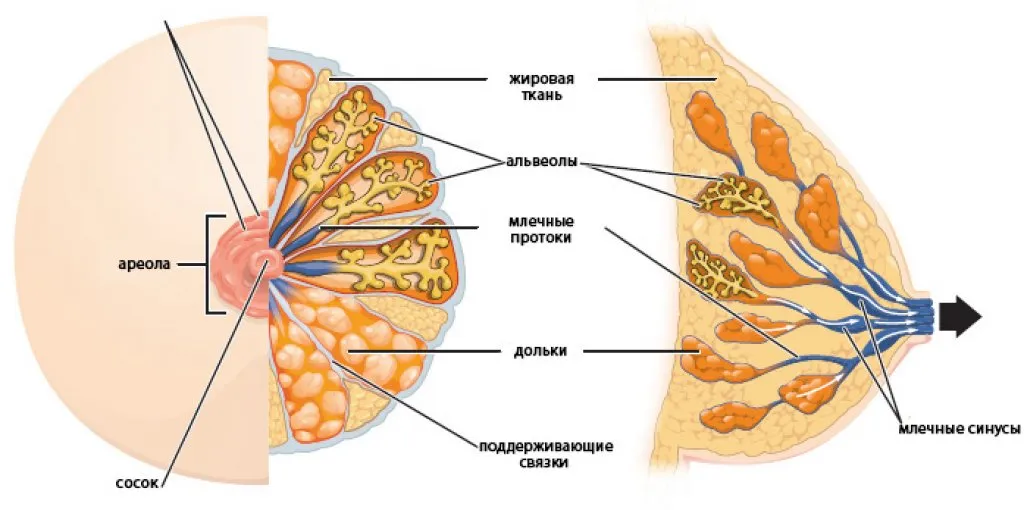

Аномалии молочной железы: медицинские примеры и визуализация

Раздел: Мудрость в деталях